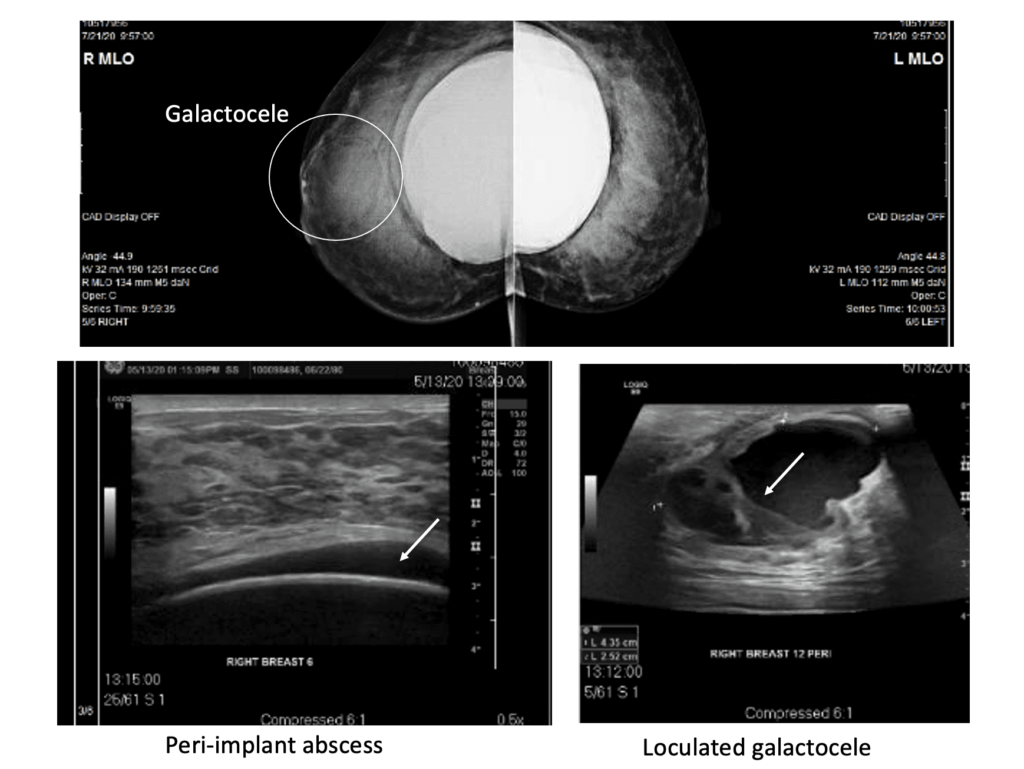

The below series of images demonstrate the unfortunate and unusual infection of a breast implant as a result of countless aspirations of a galactocele rather than definitive drainage. Fortunately, the patient did well and continued to breastfeed for years after this removal of the infected implant. But it was a 100% preventable issue. We detail more of her case in this report in a plastic surgery journal.

Galactoceles are true milk-retention cysts that develop most often in the setting of hyperlactation and pumping. Whereas early galactoceles may contain more simple milk, more chronic galactoceles ultimately can develop a collection of extremely thick, semi-solid material. They present with most often a painless swelling in a particular region of the breast and should be confirmed with ultrasound. Patients may be recommended to undergo aspiration, but this almost never resolves the collection and it refills quickly. They are drained as above.